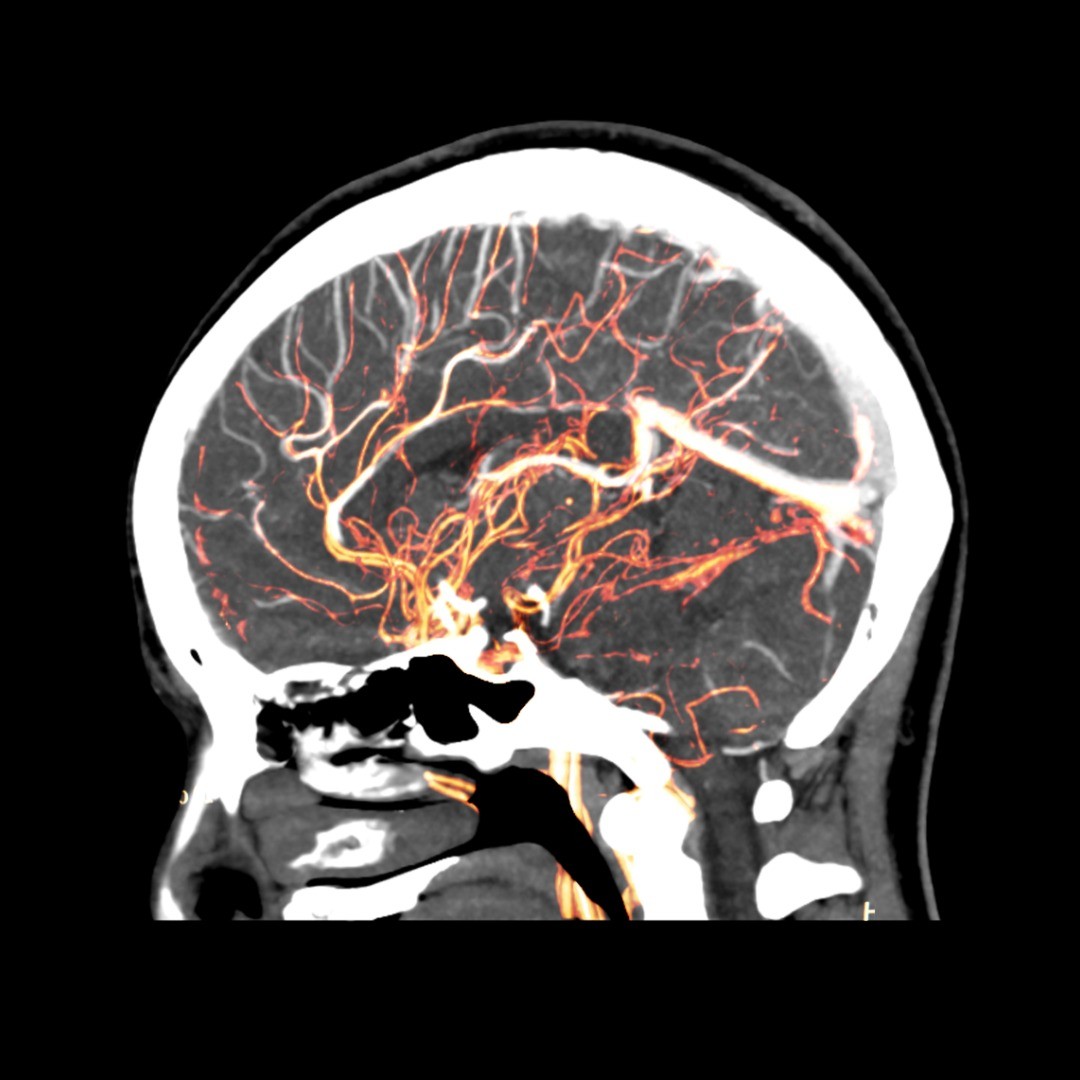

Cerebral aneurysm treatments depend on a variety of factors: whether the aneurysm, a bulge in the wall of the artery, is pre-rupture or after an event, your health and age, how small or large the aneurysm is, and whether it is causing neurological symptoms among other risk factors.

Aneurysm Clipping – In this brain aneurysm treatment, a neurosurgeon places a small surgical clip around the base of an intracranial aneurysm, blocking off the flow of blood to the aneurysm and limiting the likelihood of it bursting. Surgical clipping is a long-established medical procedure for treating both ruptured and pre-ruptured aneurysms.

Surgical Clipping – During this surgical procedure, a tiny clip is attached to the base of the aneurysm to prevent blood flow— thereby decreasing the likelihood of it bursting or rupturing if it’s pre-rupture or to treat a ruptured aneurysm. To reach the aneurysm, the neurosurgeon performs a small craniotomy, which temporarily removes a portion of the skull, and an incision in the brain covering called the dura mater allows the surgeon to carefully retract the brain and trace the affected artery to the aneurysm. Once there, the clip is placed on the neck of the aneurysm.